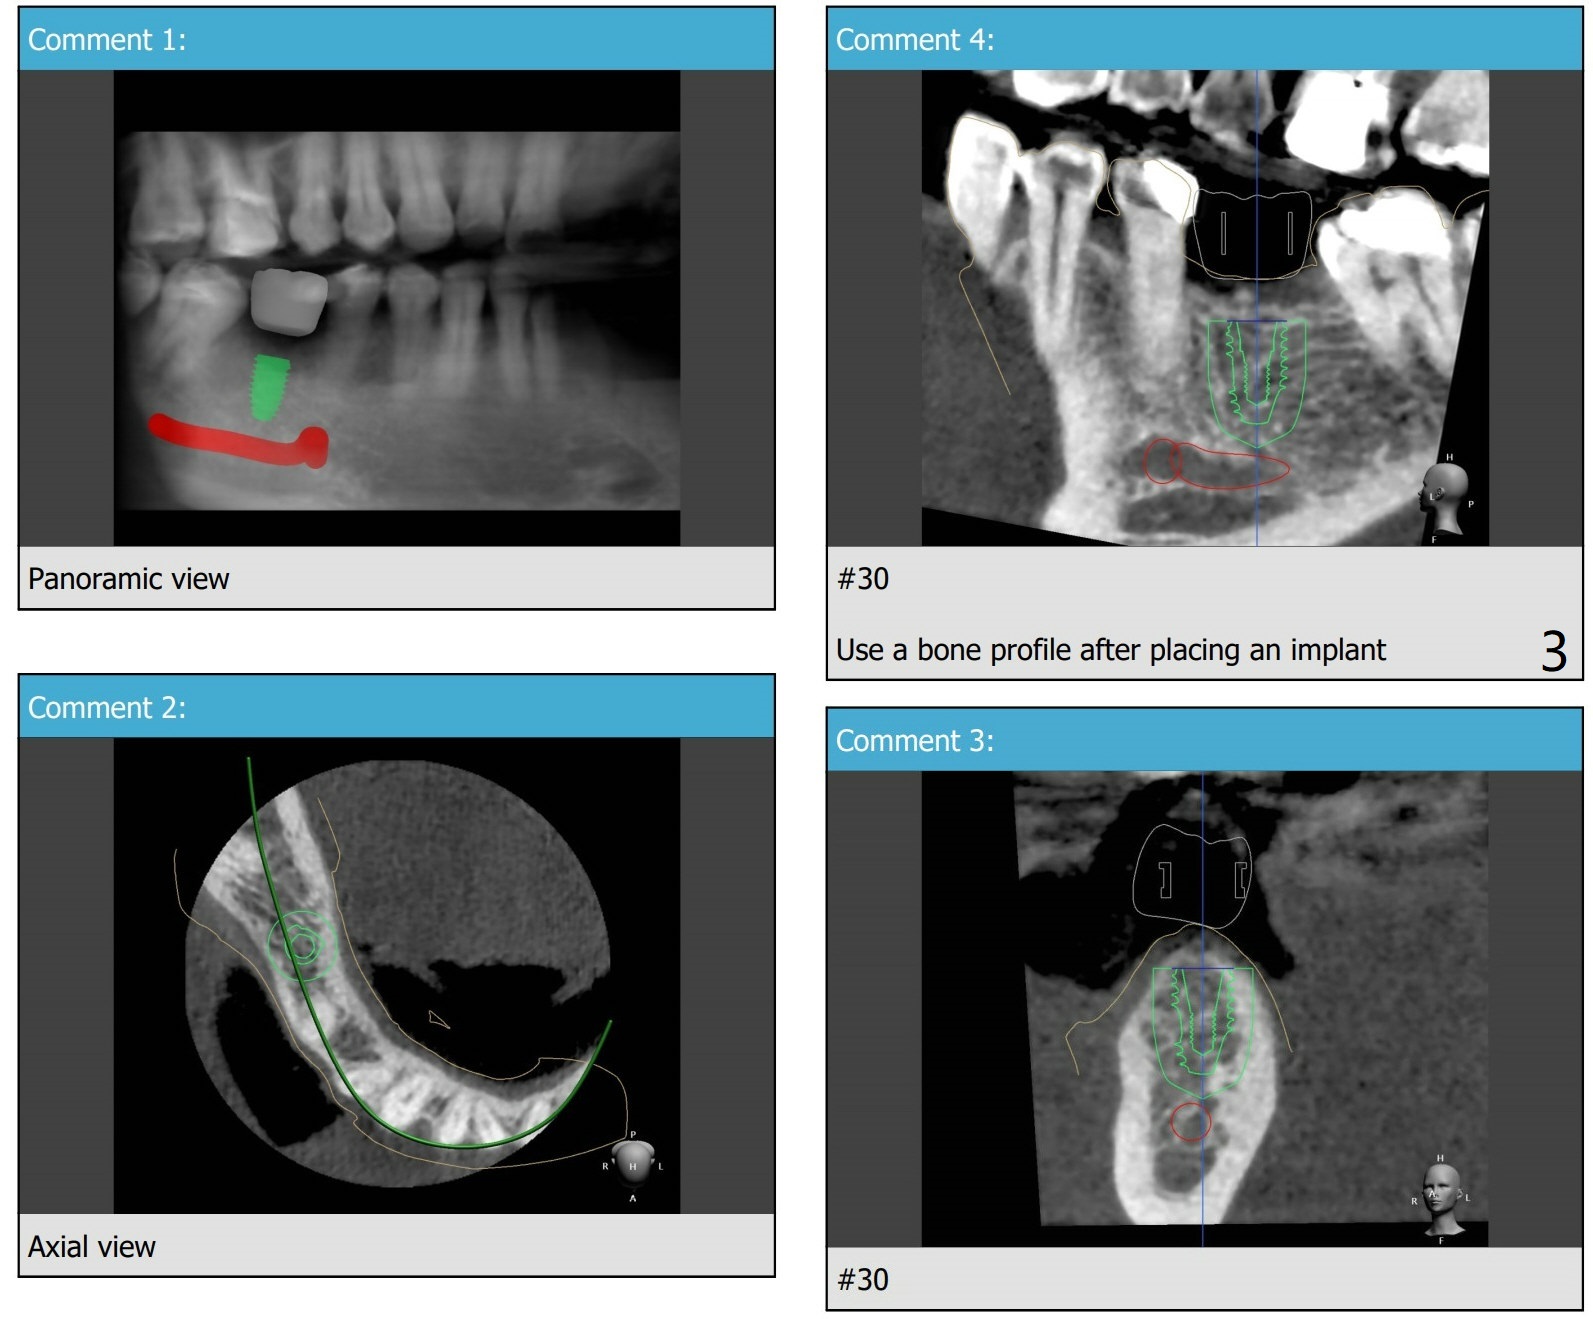

Extraction With No Bone Graft

A 45-year-old woman with #30 missing (~ 4 years, extraction without bone graft) requests treatment.